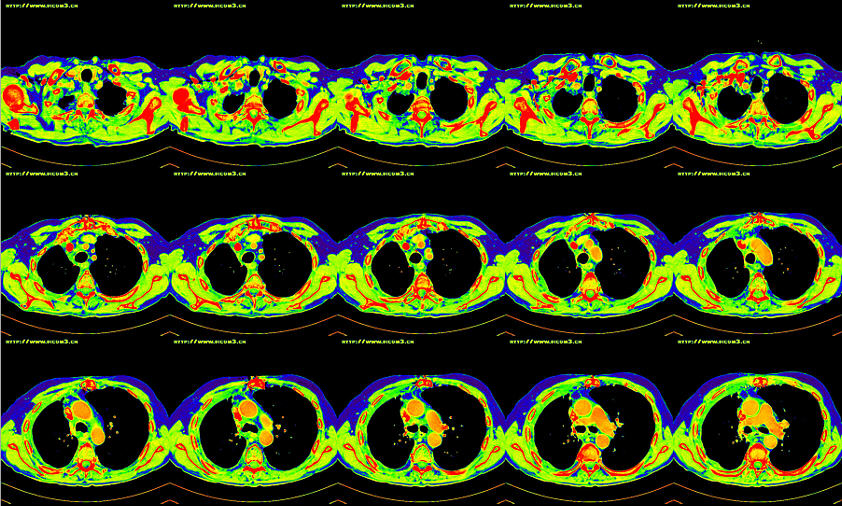

TCIA-TCGA-OV 癌症CT影像数据

TCIA-TCGA-OV 是一个癌症CT影像数据,源自癌症数据项目 The Cancer Genome Atlas (TCGA),旨在对各种类型的癌症诊治过程进行全程数字化的跟踪,以数字档案的形式记录检查结果、处方和疗效。